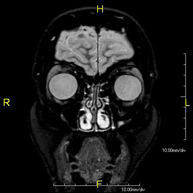

Prueba diagnóstica no invasiva que consiste en la obtención de imágenes de alta definición anatómica del cerebro mediante el empleo de un campo electromagnético y ondas de radio (con un emisor y un receptor). No utiliza radiación ionizante. Indicaciones: problemas vasculares, pérdida de memoria, epilepsia, cefalea, malformaciones, sospecha de tumor, meningitis. - RM Cais

Prueba diagnóstica no invasiva que consiste en la obtención de imágenes de alta definición anatómica del cerebro mediante el empleo de un campo electromagnético y ondas de radio (con un emisor y un receptor). No utiliza radiación ionizante. Se realiza, posteriormente, una medición cualitativa y cuantitativa de varios metabolitos (sustancias), que permitirán caracterizar las lesiones. Indicaciones: tumores, trastornos metabólicos, infecciones, epilepsia.